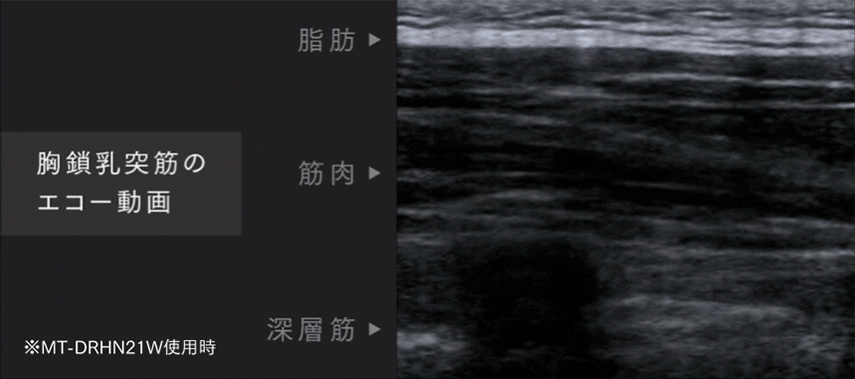

EVIDENCE

エコーによる検証動画

EMSで筋肉の奥深くまで動いています。

本当に低周波が奥深くまで届いているの?